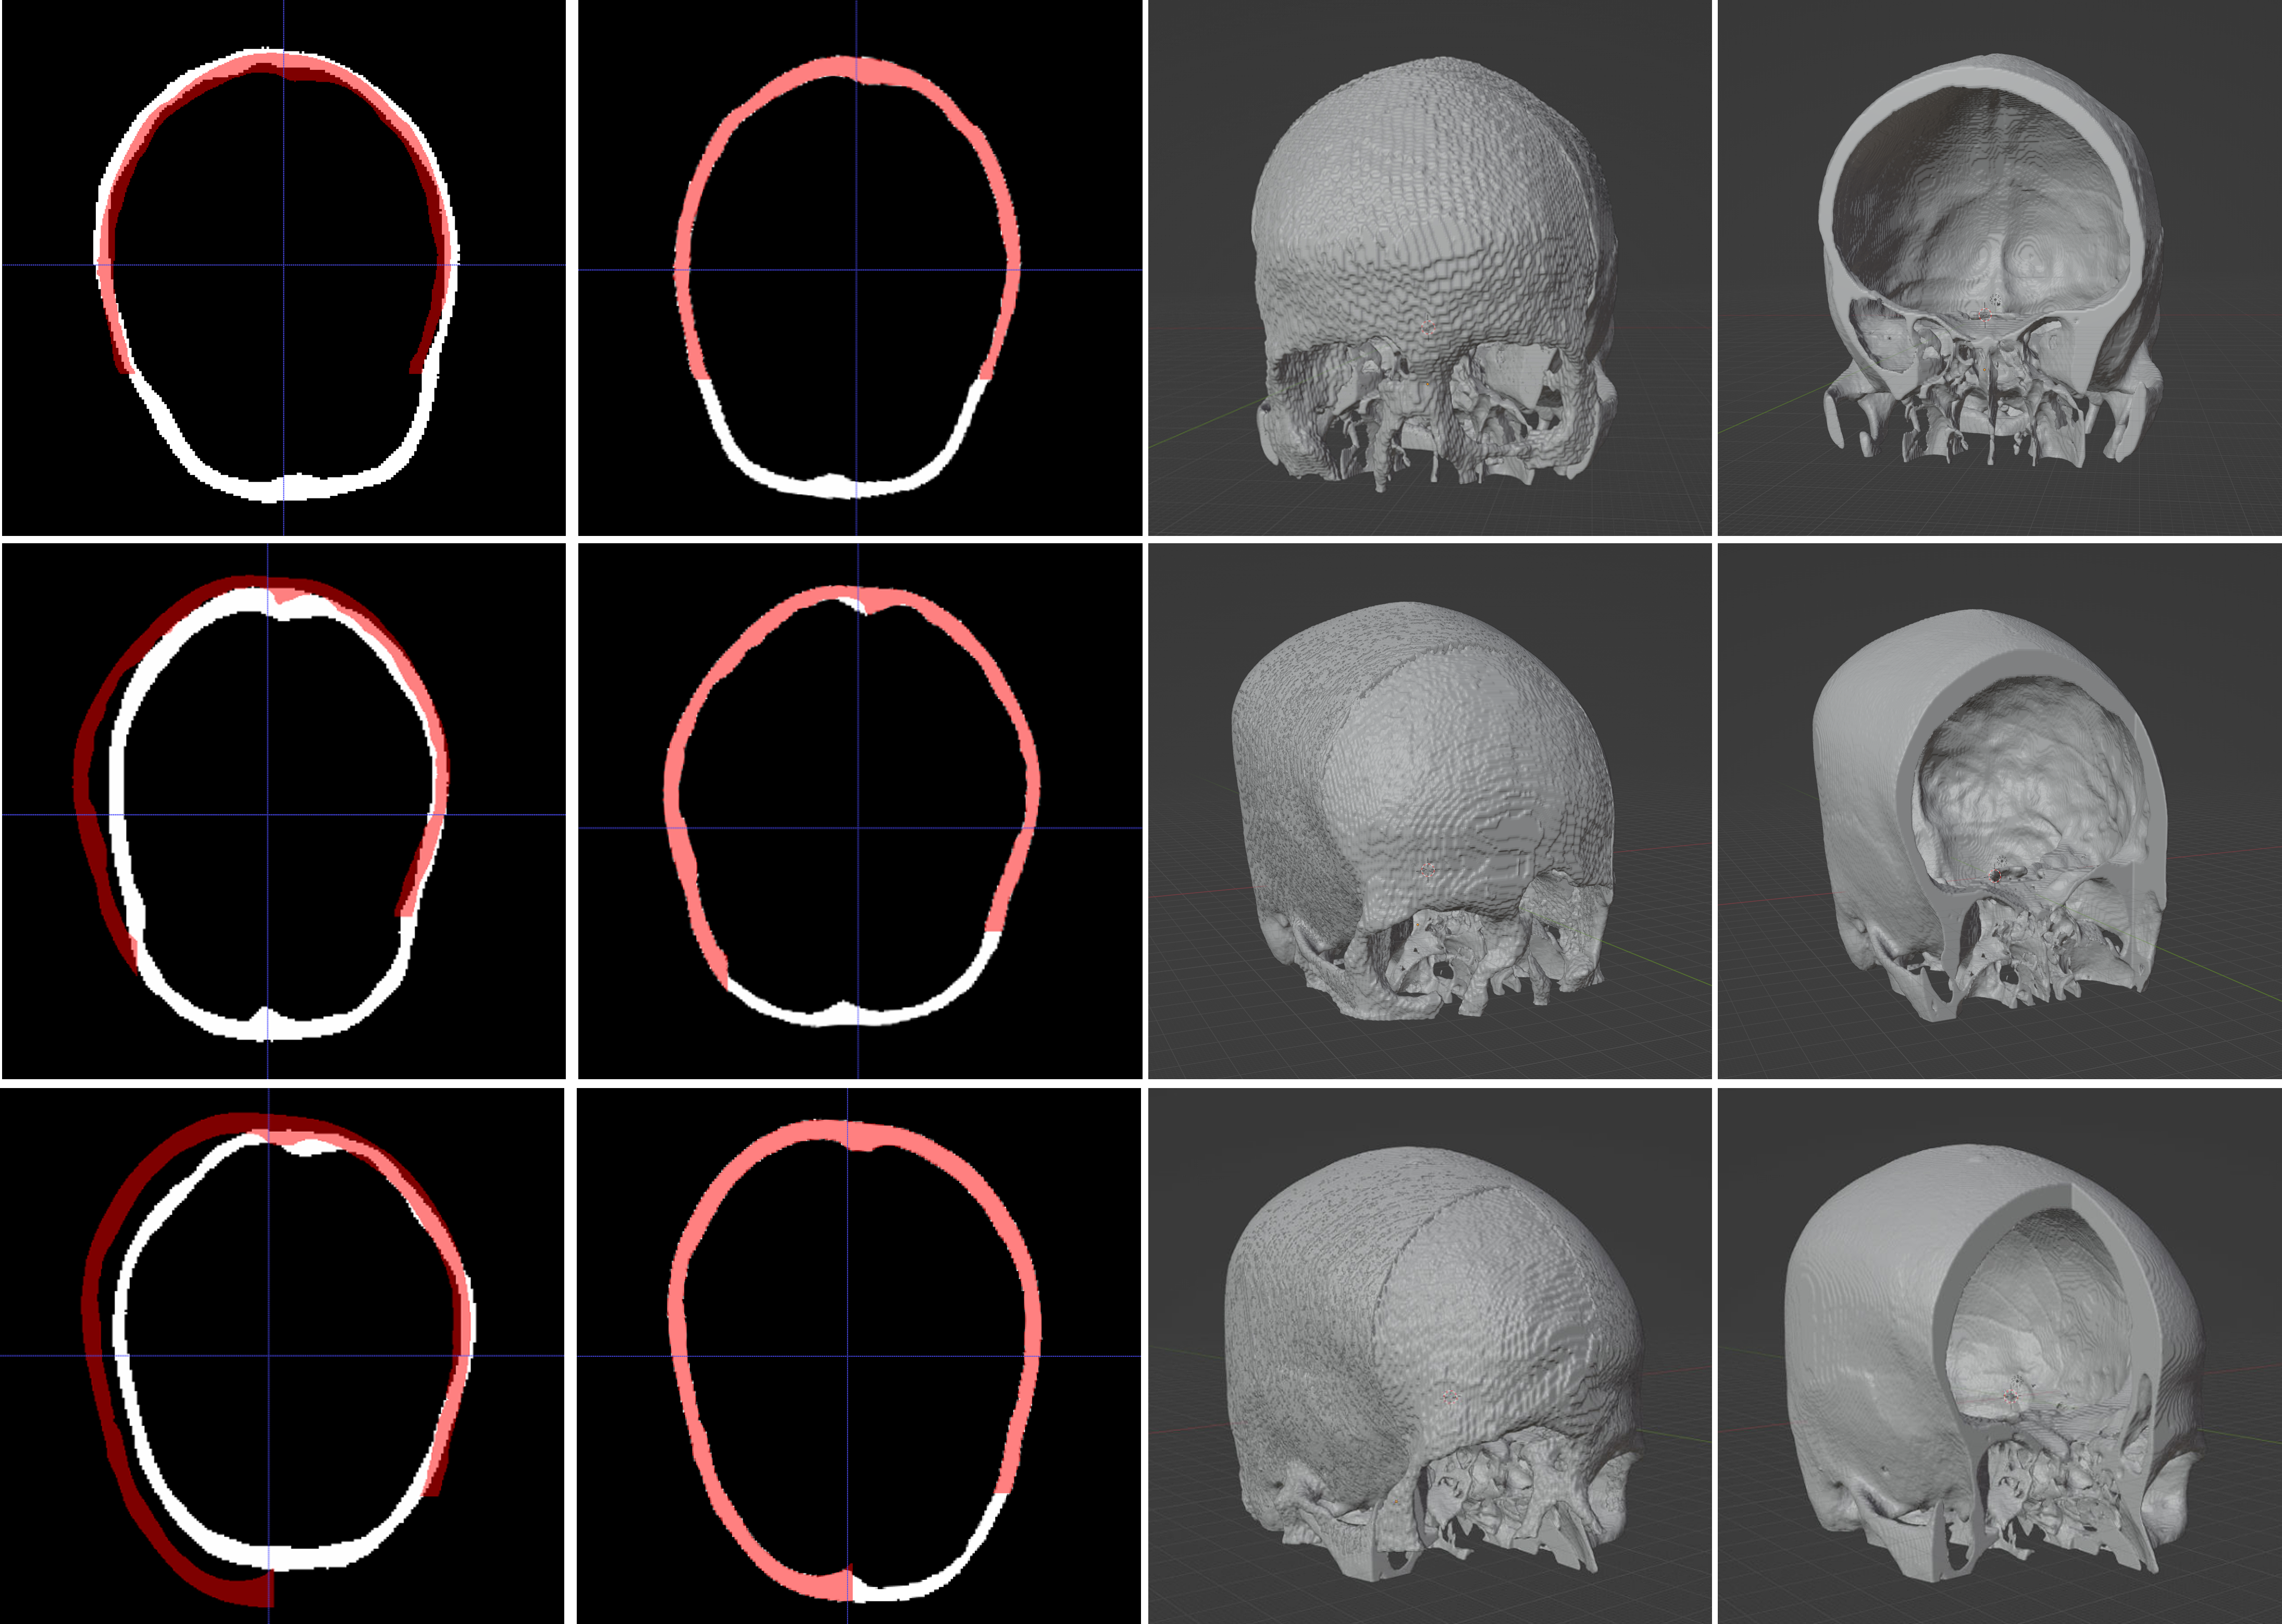

Figure 4 shows the reconstruction of cranial and facial defects for the MUG500+ dataset, using the trained model. We can see that the cranial reconstruction is satisfactory, while the network failed to recover the subtle and complex facial structures. Besides the learning capacity of the network, we attribute the unsatisfactory facial reconstruction performance largely to the MUG500+ dataset itself, as the MUG500+ skulls have obvious artifacts (e.g., spine, catheter extruded from the patients’ mouth, etc, as can be seen from the last column of Figure 4.) that can potentially distract the network from learning the skull geometries. The removal of these artifacts in a preprocessing procedure is non-trivial, since they are closely connected with the skull, and therefore difficult to be separated from the area of interest (e.g., facial bones). One option to better utilize the dataset for cranial implant design is to crop (axially) and discard the entire facial area of the skulls as in [15].

On the contrary, the SkullFix dataset contains mostly artifacts-free skulls, and is more suitable for the facial reconstruction task than MUG500+. The last column in Figure 5 shows skulls with facial defects. We can see that part or the entire facial structures are missing. The first to third column in Figure 5 show the facial reconstruction results obtained using the trained network. Note that the initial reconstruction and the input are misaligned (first column, Figure 5), and therefore the missing facial bones cannot be obtained via a subtraction procedure. We address this by registering the reconstructed completed skull with the input defective skull using a similarity transformation. The second column in Figure 5 shows the geometry alignment results. Note that the registration is unsuccessful for some cases. The third column in Figure 5 shows the facial reconstruction in 3D. We can see that, compared with the results on MUG500+, the network can learn to restore most of the missing facial structures on the artifacts-free dataset more effectively. Note that the registration step could be avoided by properly aligning the geometry information in the NIfTI output from the model with that of the original NRRD test samples.A 3D viewer for interactive inspection of the skull models can be accessed at https://proj-page.github.io/softwarex_monai.html.